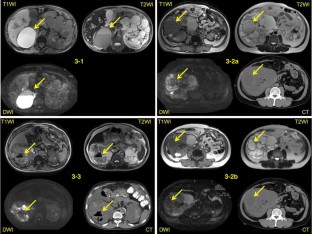

There were 24 patients with cyst infection (36 infected cysts) and 12 patients with acute cyst hemorrhage (13 bleeding cysts). White blood cell (WBC) count >10,000/μl, serum C-reactive protein (CRP) >15.0 mg/dl, and body temperature >38 °C strongly suggested cyst infection. All of the cysts with hemorrhage contained a high-density mass-like area or showed overall high density on CT, and all patients with cyst hemorrhage had abdominal pain or gross hematuria. On the other hand, infected cysts showed an increase of intensity on MRI [diffusion-weighted imaging (DWI)], while a fluid–fluid level, wall thickening, and gas were also evidence of infection. Abdominal pain and/or sequential changes on MRI after onset of symptoms were useful for localizing infected cysts.

Fig. 2